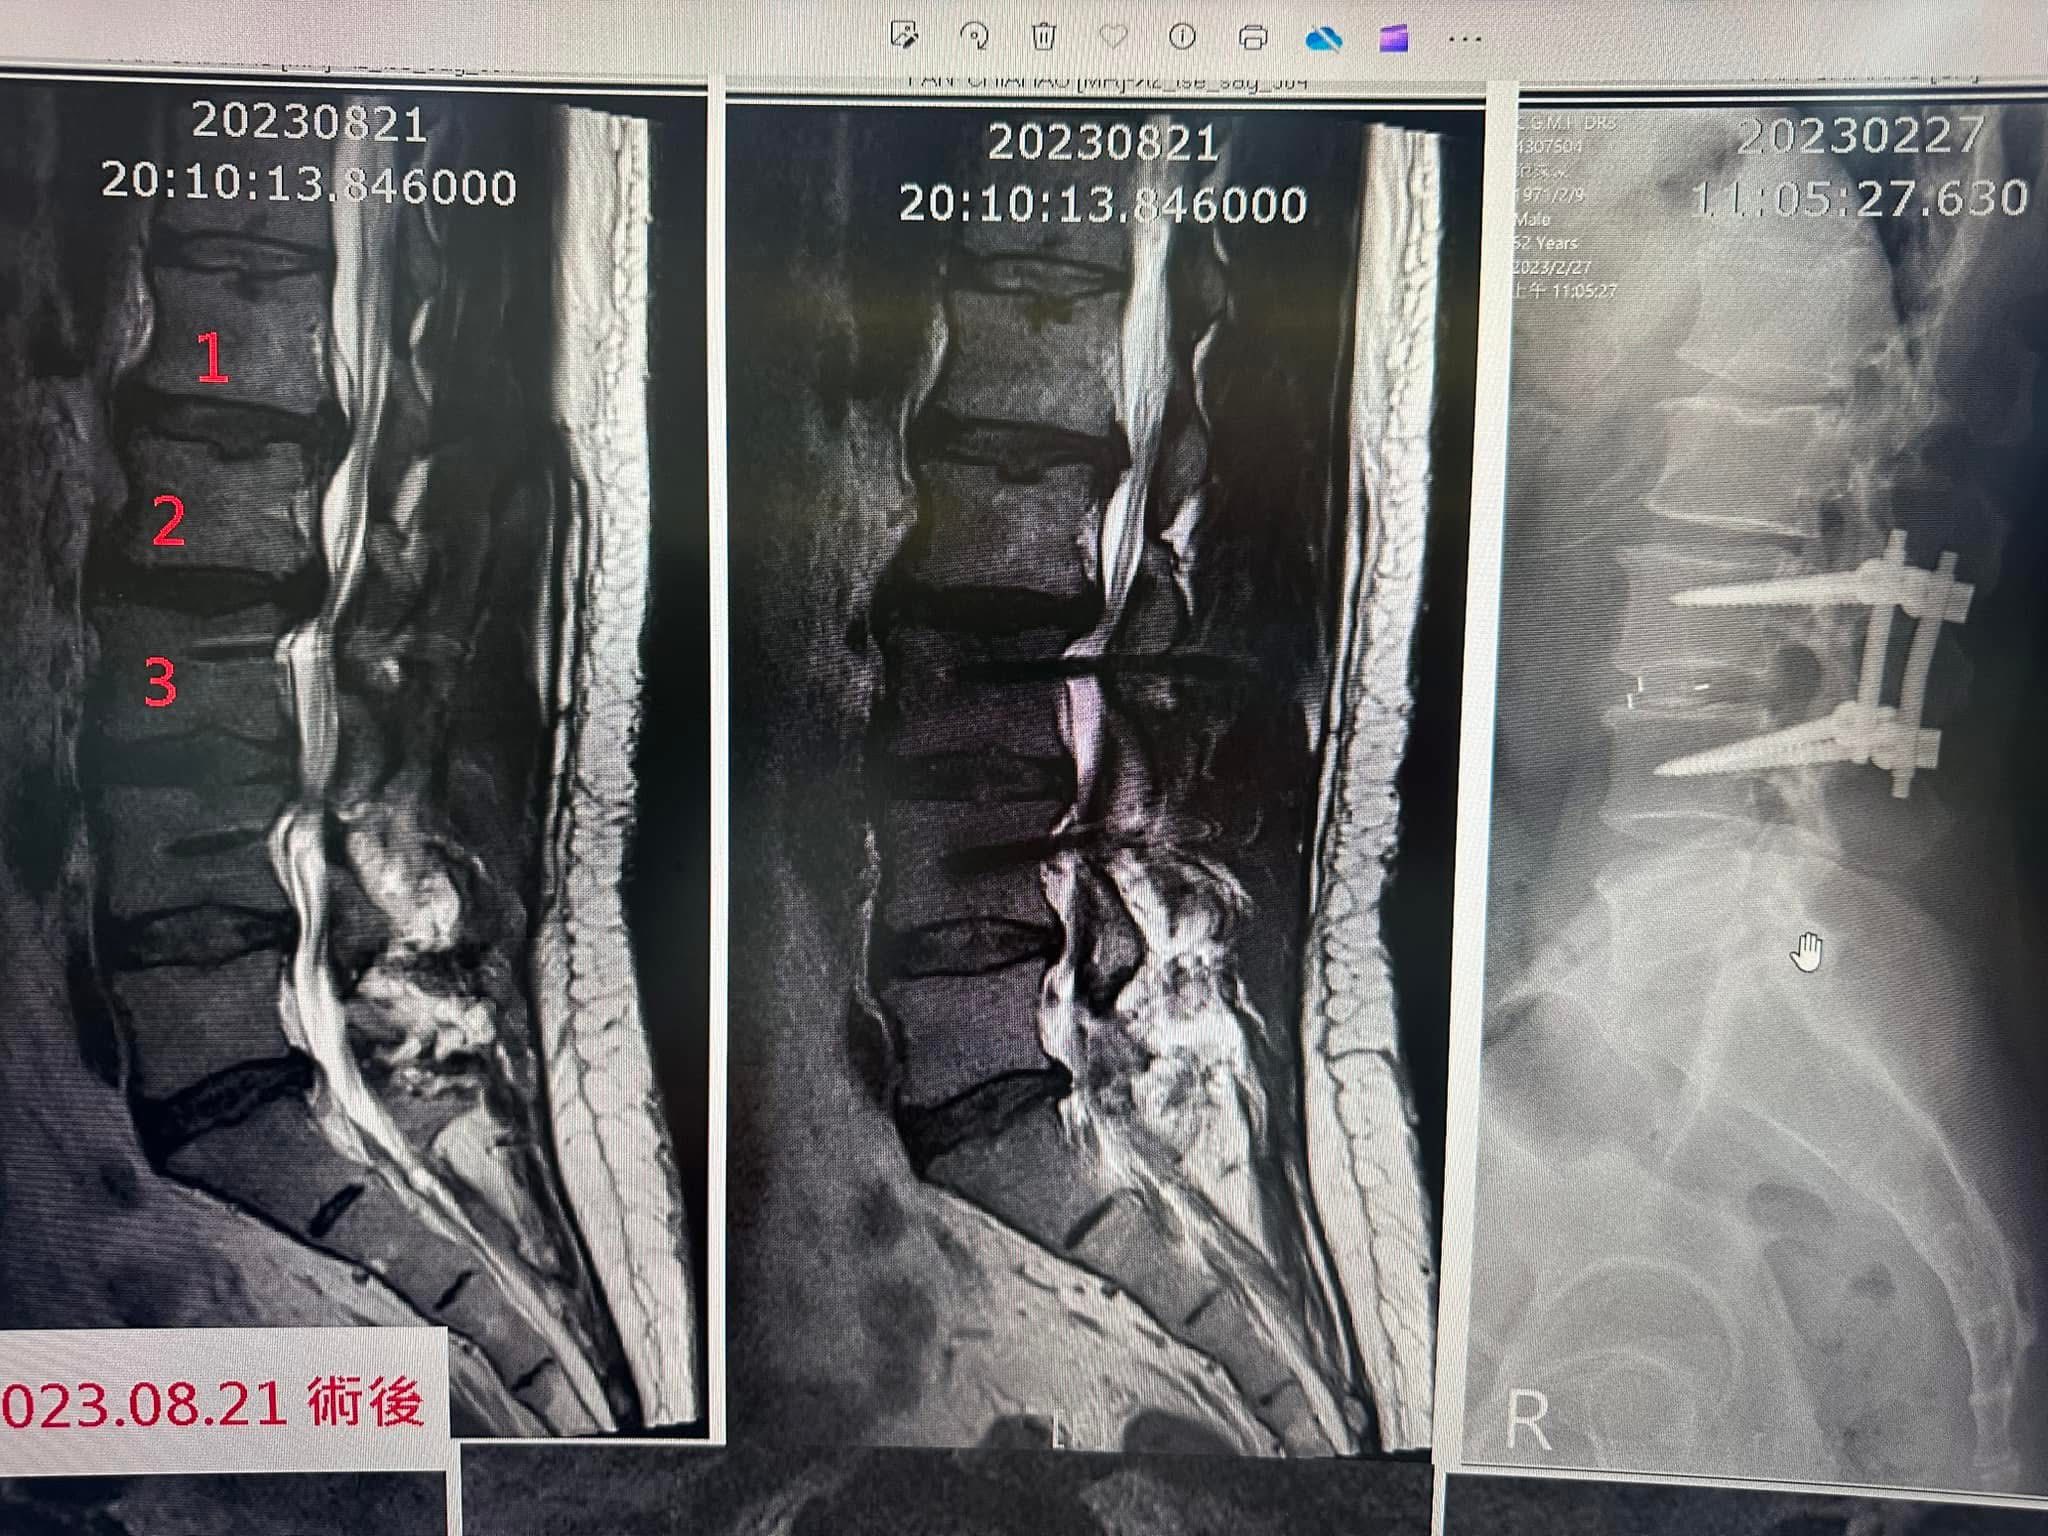

Cervical Spine Treatment Cases 腰椎治療案例 「一幅瓢瓜水墨,記錄了一段不用開刀的人生轉彎。山水之外:一位水墨大師與他的腰椎故... 2025.12.23 【醫療現場】脊椎手術後的無聲痛哭:短時間三次動刀與癱瘓的代價——當手術刀無法解決... 2025.11.25 醫師的沉思:當長輩開始走路越走越彎 腰椎滑脫與狹窄的四大症狀警訊一定要看懂 【文... 2025.11.18 你的背痛,真的是一場「世紀大騙局」嗎? —— MRI是共犯?醫師被蒙蔽?椎間盤根本是... 2025.10.30 🌿特殊醫案|她以為是椎間盤突出或足底筋膜炎,但其實是Vit B6服用過量中毒 ⁉️維他命... 2025.10.22 椎間盤突出逆轉勝:從「破裂」到「復原」的醫學證據。 一位針刀醫師的真實告白。 椎... 2025.10.20 為什麼神經傳導檢查這麼重要? 為什麼說黃金治療期就是100天內? 為什麼核磁共振影像... 2025.10.20 醫案故事:高球名將Tiger Woods 的第七刀 ——當傳奇背後,是一條被切七次的脊椎 老... 2025.10.16 美國開腰椎手術要兩百萬?VS 台灣三週針刀療程的奇蹟 2025.09.23 五年之內歷經三次脊椎大刀之後的醫療反思。 下背手術失敗綜合症候群的一些觀點 脊椎微... 2025.09.22 「脊椎手術有它的價值,但不是每個人都需要大刀──針刀療法給病人多一個選擇」 📌 脊... 2025.09.18 #巨大椎間盤突出一定要開刀嗎? #三家醫院骨科醫師說很嚴重需要手術 #難道真的沒有第... 2025.09.17 ⭕️巨大椎間盤突出,PRP治療失敗、痛到掰咖…他差點走上手術台,卻在這裡看見奇蹟 ⭕️醫... 2025.09.07 【少棒奪冠、脊椎隱憂與台灣棒球的困境】🇹🇼⚾️ 「睽違29 年後的淚水,背後卻有個殘酷... 2025.08.25 ✈️【一張差點被腰痛奪走的法國機票】 ✅一張飛往法國的機票,因為「腰椎管狹窄」而延宕... 2025.08.21 1 2 3 4 5 下一頁 →